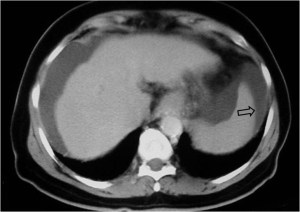

Esta segunda imagen corresponde a ascitis. Observa como la interfase entre el bazo y el líquido (flecha) es más nítida que en la imagen anterior. También lo es la interfase entre el hígado y el líquido.